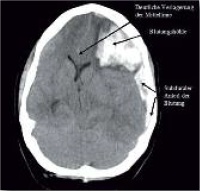

Pennig führte an, dass inzwischen mehr als 1.000 Patienten, die in deutschen Kliniken versorgt worden sind, einen Eindruck davon vermittelt hätten, wie die medizinische Kriegswirklichkeit aussehe und wie anders das Spektrum der zu versorgenden Verletzungen im Vergleich zu früheren Auseinandersetzungen inzwischen sei.

Schwerere Verletzungen und perfide Kampfstrategien

Sowohl innere Verletzungen als auch Oberflächenverletzungen seien andersartig und ungleich schwerwie­gen­der als sie noch aus dem 1. und 2. Weltkrieg medizinisch bekannt und dokumentiert seien. Das gilt bei­spielsweise für die Folge von Phosphorbomben, die – obgleich geächtet – im Ukrainekrieg zum Einsatz ge­kommen sind (EAPCCT-Kongress).

Pennig erläuterte auch die ­– wie er es nannte – „perfide Strategie der Hersteller von Minen“, die ganz gezielt demjenigen, der auf sie tritt, „nur“ beide Beine wegreißen. Während früher eine Mine darauf ausgerichtet war, denjenigen, der darauf trat, zu töten, soll jetzt die Kampftruppe im Umfeld mitgeschwächt werden. Denn der so Verletzte benötigt sofortige Versorgung und einen Transport – was weitere Kräfte bindet.